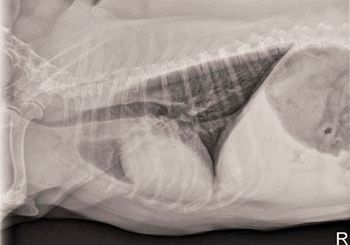

Examine the imaging results to help solve this pug's problem.